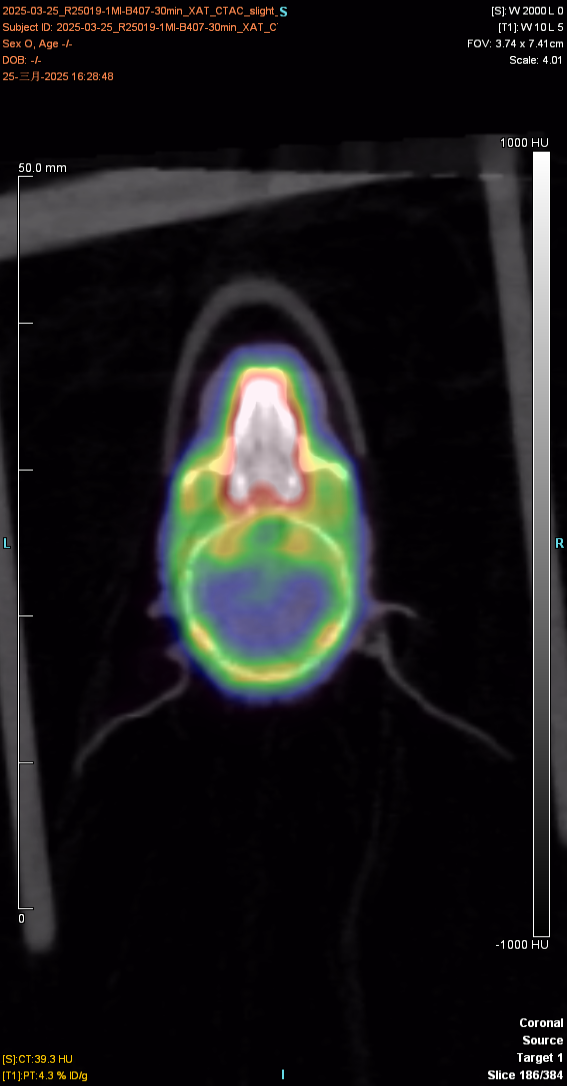

The figure below shows the 30min imaging image

The experimental animal was a mouse, provided by Huajing, with a weight of about 23g and mal♠e. After injection of the drug and anesthesia, PET scan was performed to collect images and obtain the distribution map of the drug in÷ the body. After imaging, the experimental animal gradually woke up and€ returned to normal, with good diet, two excreta and mental s£tate.